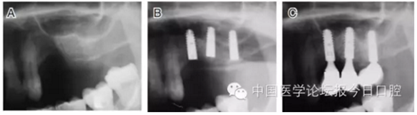

病例5 多顆種植體(圖7)

圖7